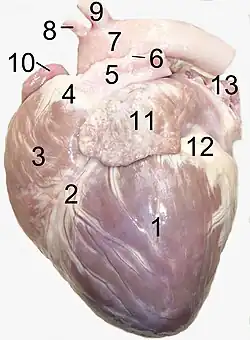

Anatomie

Die Gestalt des Herzens gleicht einem abgerundeten Kegel, dessen Spitze nach unten und etwas nach links vorne weist. Das Herzvolumen entspricht ungefähr dem Volumen der geschlossenen Faust[19] des betreffenden Menschen. Das Herz sitzt beim Menschen in der Regel leicht nach links versetzt hinter dem Brustbein. In seltenen Fällen ist es nach rechts versetzt (die sogenannte Dextrokardie – „Rechtsherzigkeit“), meist bei Situs inversus (also bei spiegelverkehrter Organanordnung).

Räume und Gefäße des Herzens

_de.svg.png)

Rechte und linke Herzhälfte bestehen jeweils aus einer Kammer (lat. Ventriculus cordis, (Herz-)Ventrikel, kurz RV und LV) und einem Vorhof (Atrium, RA und LA). Getrennt werden die Räume der Herzhälften vertikal durch die Herzscheidewand (Septum). Diese wird in die Vorhofscheidewand (Septum interatriale, Vorhofseptum) und die Kammerscheidewand (Septum interventriculare, Ventrikelseptum) unterteilt. Außen ist die Grenze zwischen Herzkammern und Vorhöfen durch die Herzkranzfurche (Sulcus coronarius) ersichtlich, in welcher die Herzkranzgefäße verlaufen. Die Grenze zwischen beiden Herzkammern ist von außen durch zwei Furchen – Sulcus interventricularis subsinuosus und Sulcus interventricularis paracoronalis sichtbar. In den Herzkammern bildet die Herzmuskulatur netzartige kleine, in das Innere hineinragende Bälkchen, die als Fleischbalken (Trabeculae carneae, Singular Trabecula carnea) bezeichnet werden.

In den rechten Vorhof münden die obere und untere Hohlvene (Vena cava superior und inferior). Sie führen das sauerstoffarme Blut aus dem großen Kreislauf (Körperkreislauf) dem Herzen zu. Zwischen rechtem Vorhof und rechter Kammer befindet sich die Trikuspidalklappe, die bei der Kammerkontraktion einen Rückstrom des Blutes in den Vorhof verhindert. Von der rechten Herzkammer aus fließt das Blut über einen gemeinsamen Stamm (Truncus pulmonalis) in die beiden Lungenarterien. Der Rückfluss in die rechte Kammer wird durch die taschenförmige Pulmonalklappe verhindert. Die Lungenarterien führen das sauerstoffarme Blut dem Lungenkreislauf (kleiner Kreislauf) zu.

Durch meist vier Lungenvenen fließt das in der Lunge mit Sauerstoff angereicherte Blut in den linken Vorhof. Von hier aus gelangt es über eine weitere Segelklappe, die Mitralklappe, zur linken Kammer. Der Ausstrom erfolgt durch den sogenannten linksventrikulären Ausflusstrakt (LVOT) über eine weitere Taschenklappe (Aortenklappe) und die Hauptschlagader (Aorta) in den Körperkreislauf.

Herzkranzgefäße

Die linke Koronararterie (Arteria coronaria sinistra, left coronary artery, LCA) versorgt die Herzvorderseite. Sie teilt sich in einen Ramus interventricularis anterior (RIVA, left anterior descending, LAD) und einen Ramus circumflexus (RCX).

Die rechte Koronararterie (Arteria coronaria dextra, right coronary artery, RCA) gibt die A. marginalis dextra ab, welche die freie Wand der rechten Herzkammer versorgt. Am „Herzkreuz“ (Crux cordis) teilt sie sich in den Ramus interventricularis posterior und den Ramus posterolateralis dexter. Die rechte Koronararterie versorgt auch einen wichtigen Teil des Erregungssystems (Sinusknoten, Atrioventrikularknoten).

Es gibt drei große Koronarvenen, die in den Sinus coronarius des rechten Vorhofs münden und das sauerstoffarme Blut aus dem Herzmuskel abführen. Die große Herzvene (V. cordis magna) verläuft auf der Vorderseite, die mittlere Herzvene (V. cordis media) auf der Hinterseite und die V. cordis parva am rechten Herzrand. Ein kleiner Teil des sauerstoffarmen Blutes wird über die Thebesius-Venen direkt in die Ventrikel entleert.